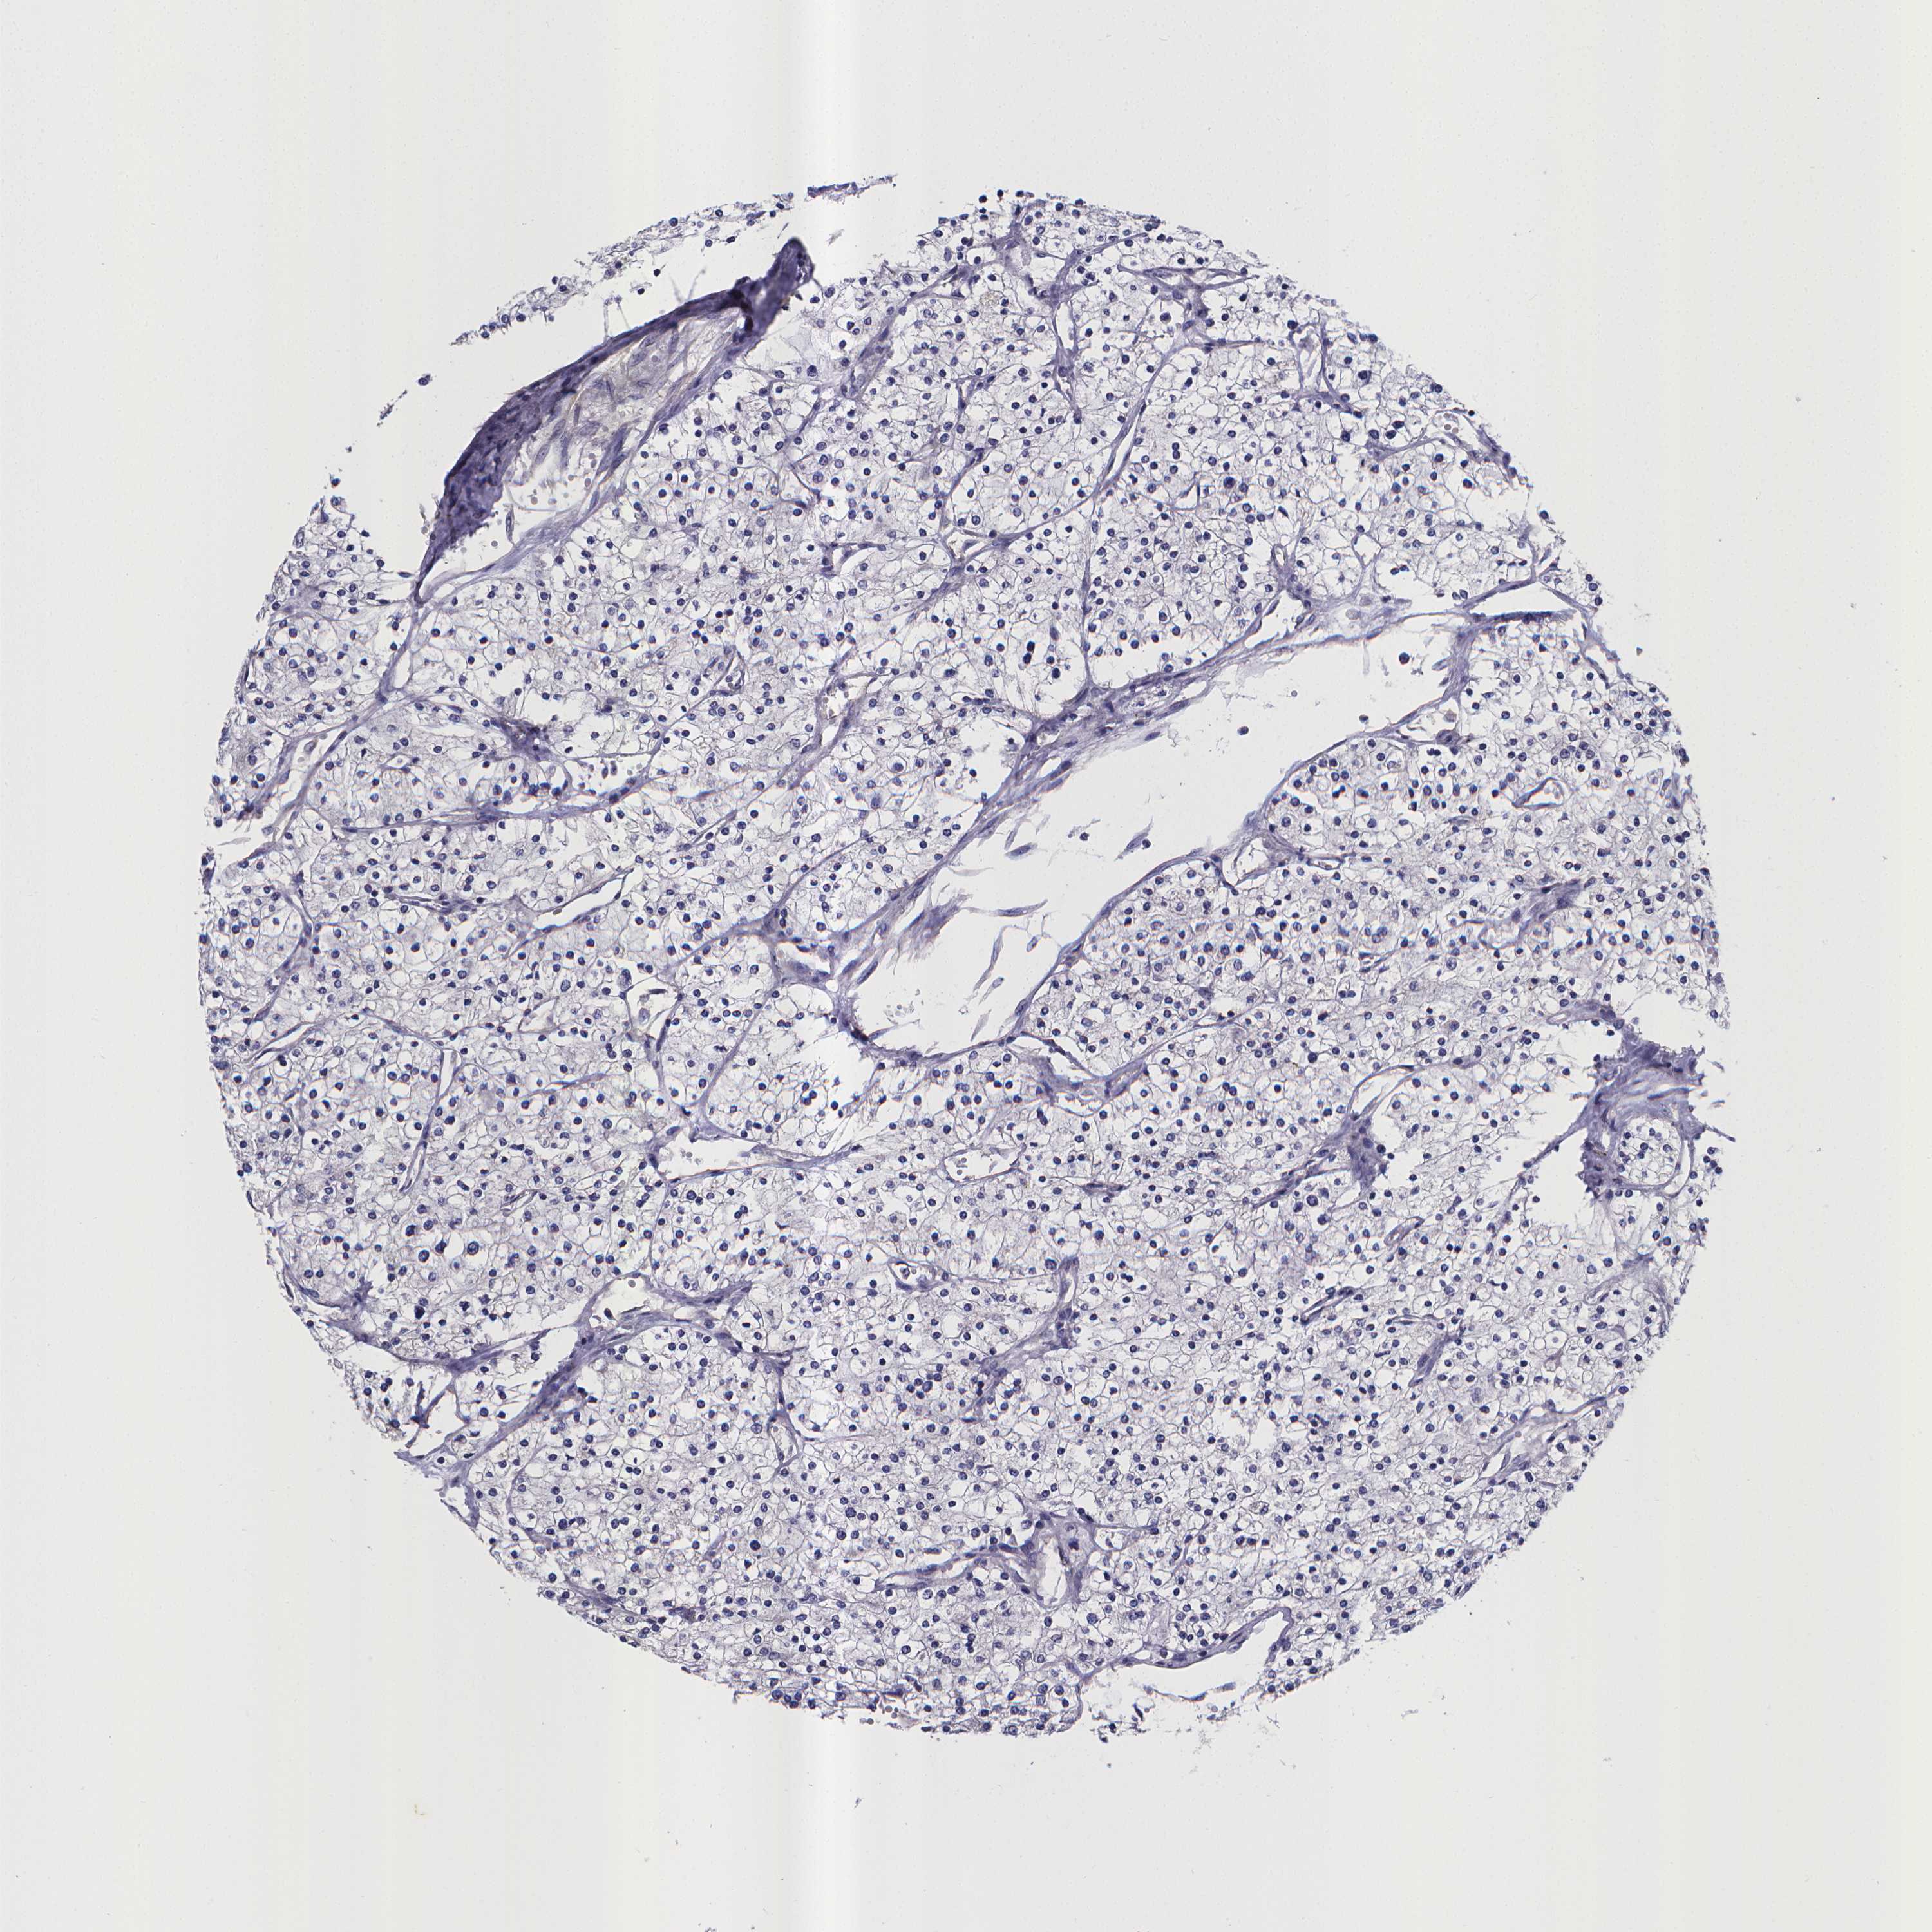

CANCER RENAL CANCER Show tissue menu

Renal cancer

Kidney renal clear cell carcinoma

KIDNEY RENAL CLEAR CELL CARCINOMA (TCGA) - Interactive survival scatter ploti

RERG is potential prognostic, high expression is favorable in Kidney Renal Clear Cell Carcinoma (TCGA)